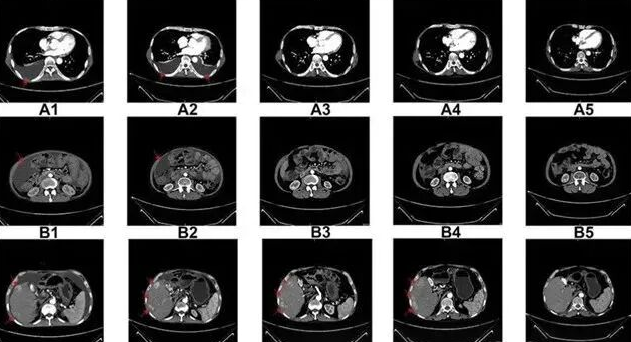

△NK细胞输入前和治疗期间的CT扫描结果

国内一名60岁的卵巢癌晚期患者,在接受了体外扩增,高度活化的同种异体NK细胞的临床治疗后,CA125水平从11,270降至580,所有腹水都消失了。此外,CT扫描的肿块体积减小,并且没有出现副作用。

一名广泛期小细胞肺癌患者,在进行4个疗程化疗和4次高度活化NK细胞临床干预后,患者第一次进行治疗后的CT复查,结果显示,肿瘤缩小到了原来的1/8。而且距发病第六年的CT复查中,仍旧没有发现任何异常及复发的迹象。